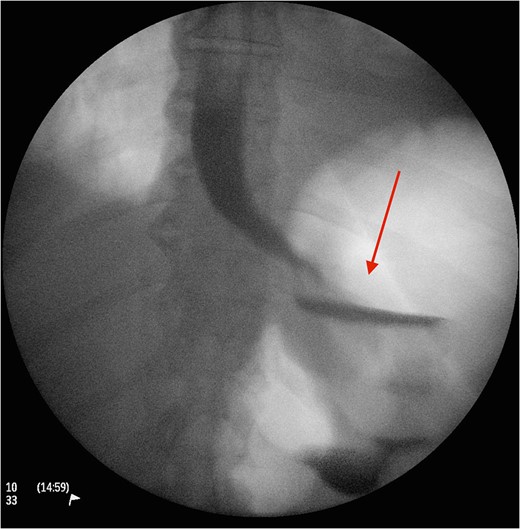

Cross section CT image demonstration the site of the band with no collection (red arrow).

CT image demonstrating the air loculation site next to the band (red arrow).